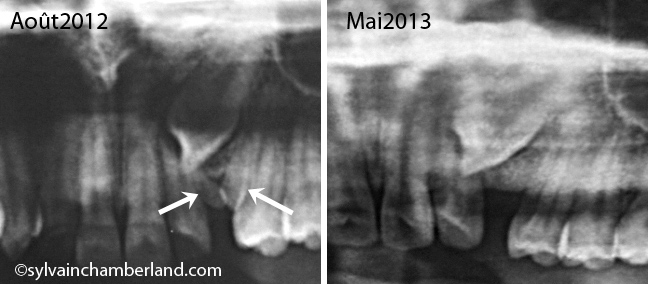

[caption id="attachment_6934" align="alignleft" width="390"]

Présence de 2 odontomes (flèches blanches) ayant empêcher l’éruption de la canine permanente.[/caption]

Les 2 minidents sont probablement des odontomes et c’est ce qui explique l’inclusion de vos canines. Il faut donc procéder à l’extraction des odontomes et faire la traction des canines incluses.